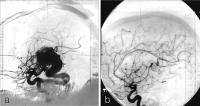

AV-Malformation - Planung für Gamma Knife

Abbildung 5a-b: 5a: AVM im Thalamus re, St. p. Blutung, St. p. Teilexstirpation, Gamma Knife-Planungsangiographie (A. carotis interna re). 5b: Kontrollangiographie (A. carotis interna re.) nach 36 Monaten, komplette Obliteration der AV-Malformation